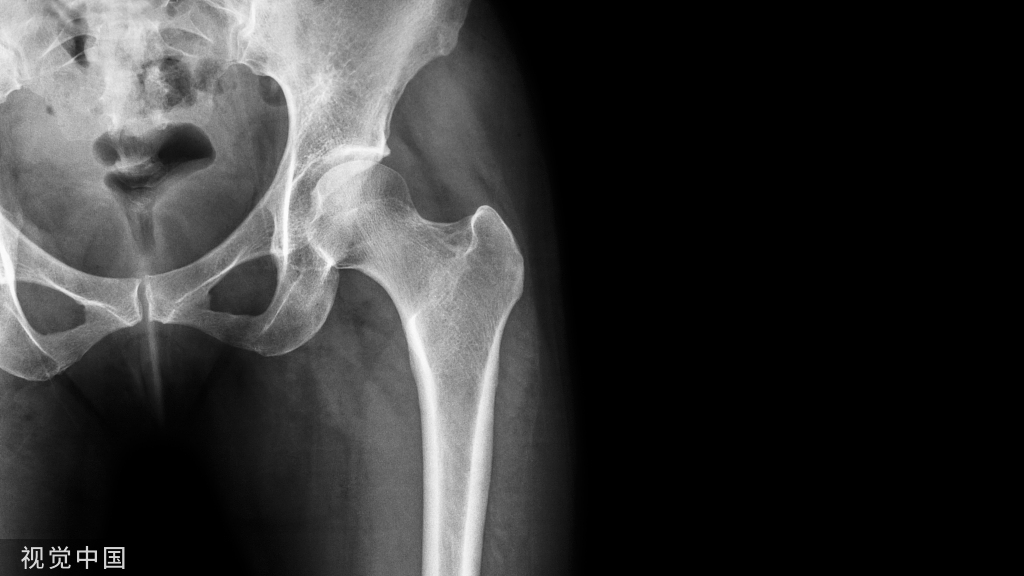

除此之外,在严重髋臼骨折股骨头中央型脱位患者中,可以沿股骨颈轴线方向进行牵引,减少股骨头髋臼中央的压力,并尽量获得一定程度上复位(图 13)。